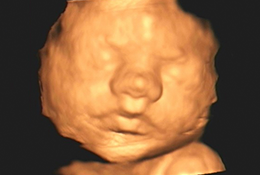

Com alta tecnologia realizamos diversos tipos de ultrassonografias: Obstétrica, Obstétrica com Doppler, Morfológica, 4D, Transvaginal, Transvaginal para pesquisa de Endometriose, Abdominal, Mamas, Tireoide e outros.